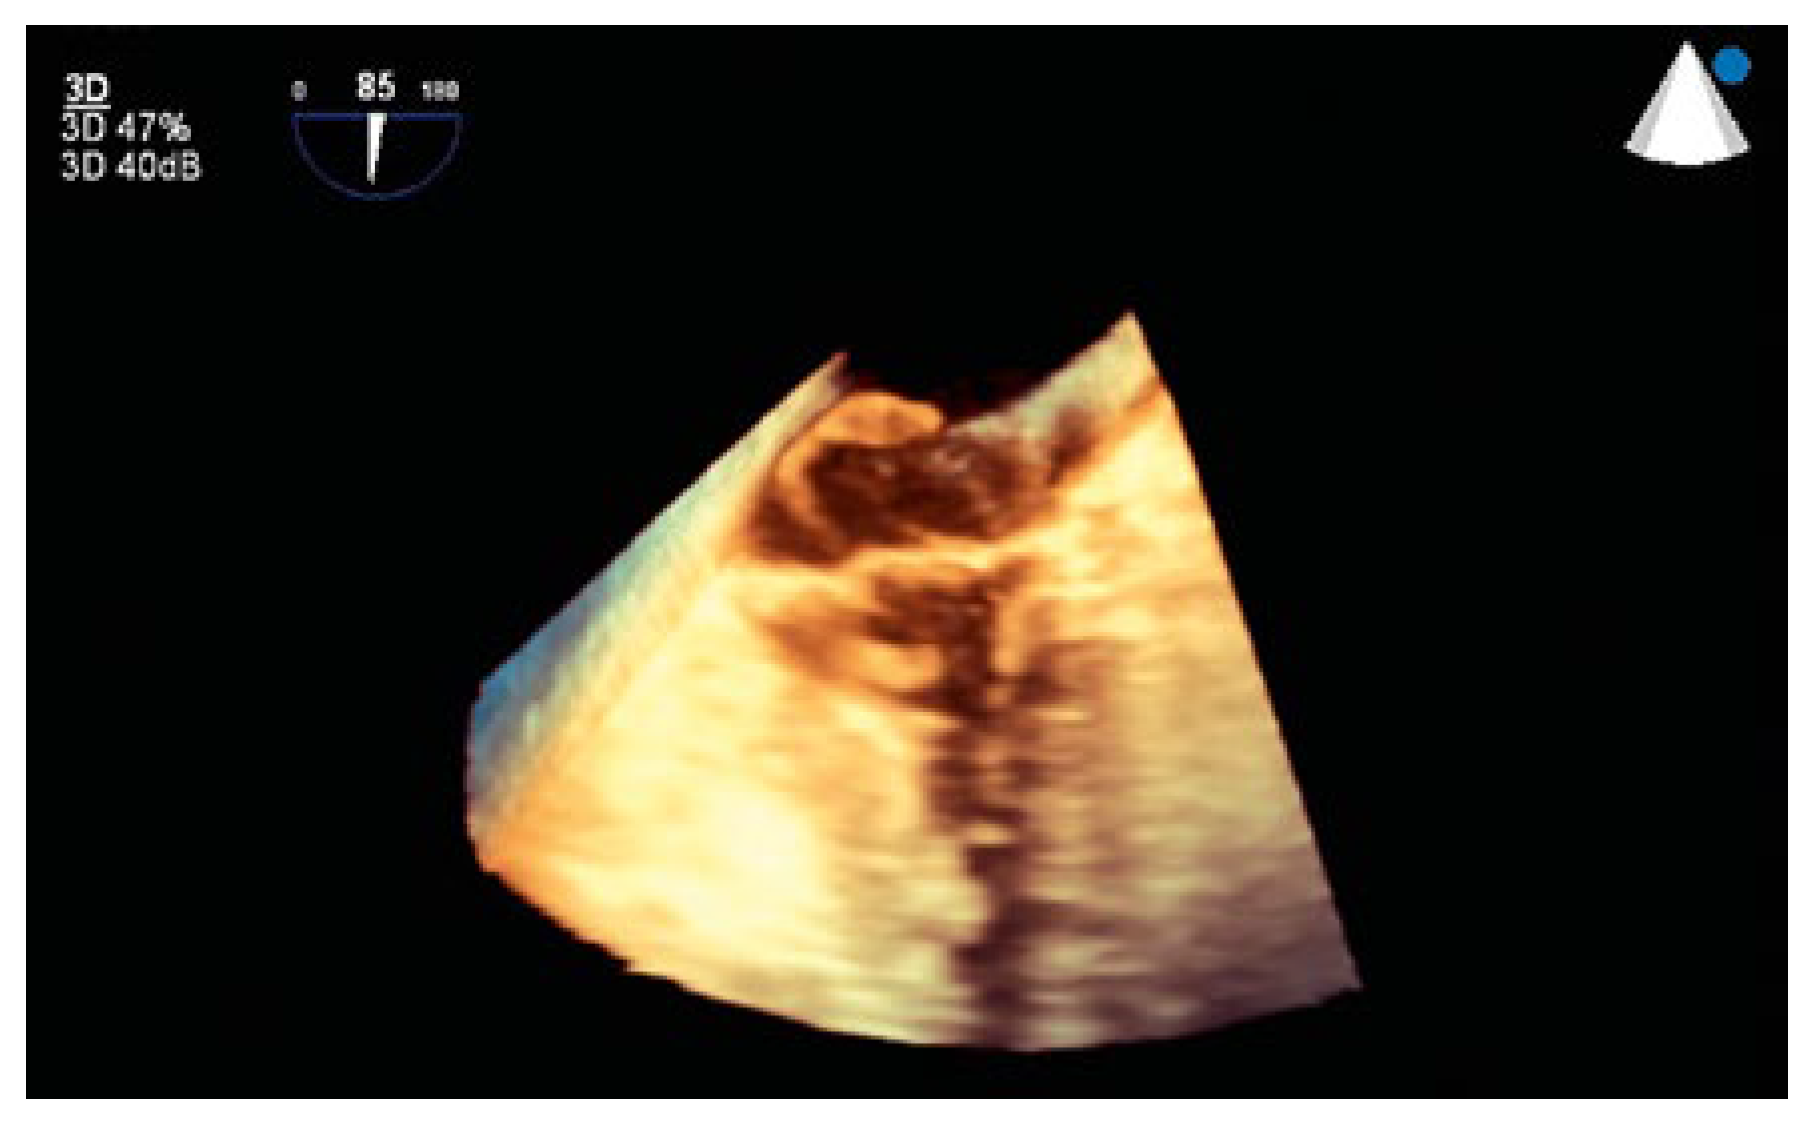

Thrombus in Transit

Case presentation